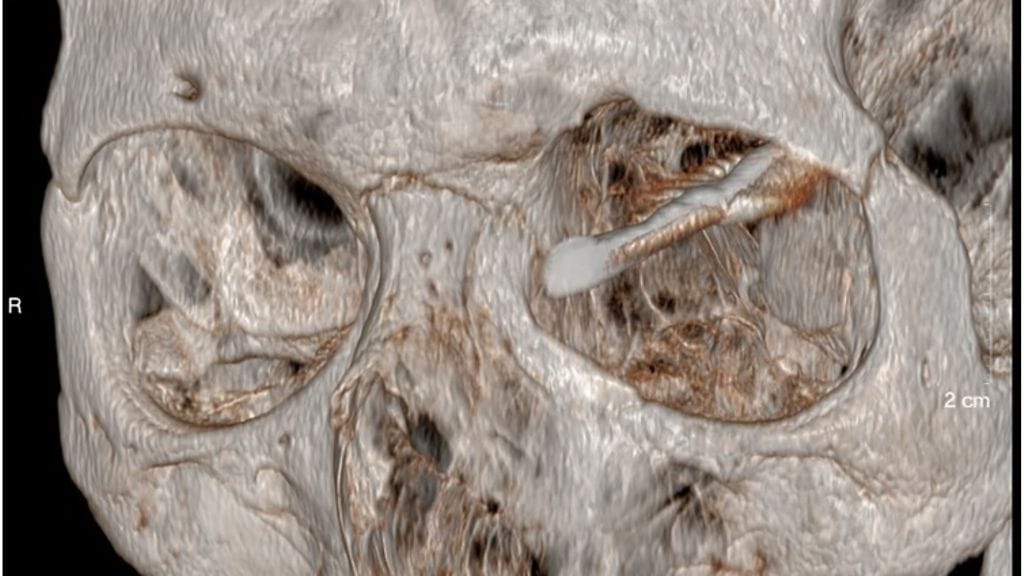

International Journal of Surgery Case Reports -julkaisussa ilmestynyt tapausraportti antaa yhden esimerkin arkiaskareissa piilevistä riskeistä. 58-vuotias italialainen mies saapui Veronassa sijaitsevaan sairaalaan naula yläluomeensa uppoutuneena. Potilas oli leikannut nurmikkoa, kun naula oli lävistänyt hänen vasemman kulmansa.

Parin senttimetrin mittainen naula teki silmän liikuttamisesta vaikeaa. Oli vain muutamasta millistä kiinni, ettei naula puhkaissut miehen silmämunaa.

Vierasesine poistettiin miehen kasvoista leikkauksessa. Kuukauden kuluttua potilaan näkökyky sekä silmän liikuttaminen olivat parantuneet normaaleiksi.

Varoitus: Kuvat voivat järkyttää.